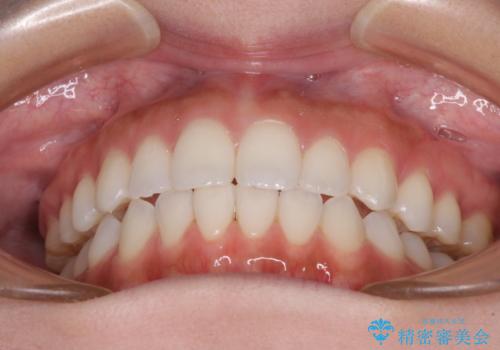

前歯のオープンバイトを治したい インビザラインでの矯正治療

- 前歯の上下スペースによる話しにくさと顎への負担を気にして来院された患者様です。

インビザラインにより上顎の大臼歯を圧下し、上下の前歯の隙間を閉じていくこととしました。

上顎の奥歯を圧下させることで、上下前歯を接触させるように計画しました。

前歯が急に接触するようになり、慣れるまで時間がかかりましたが、前歯でものが咬めるようにもなり、患者様には大変満足していただきました。